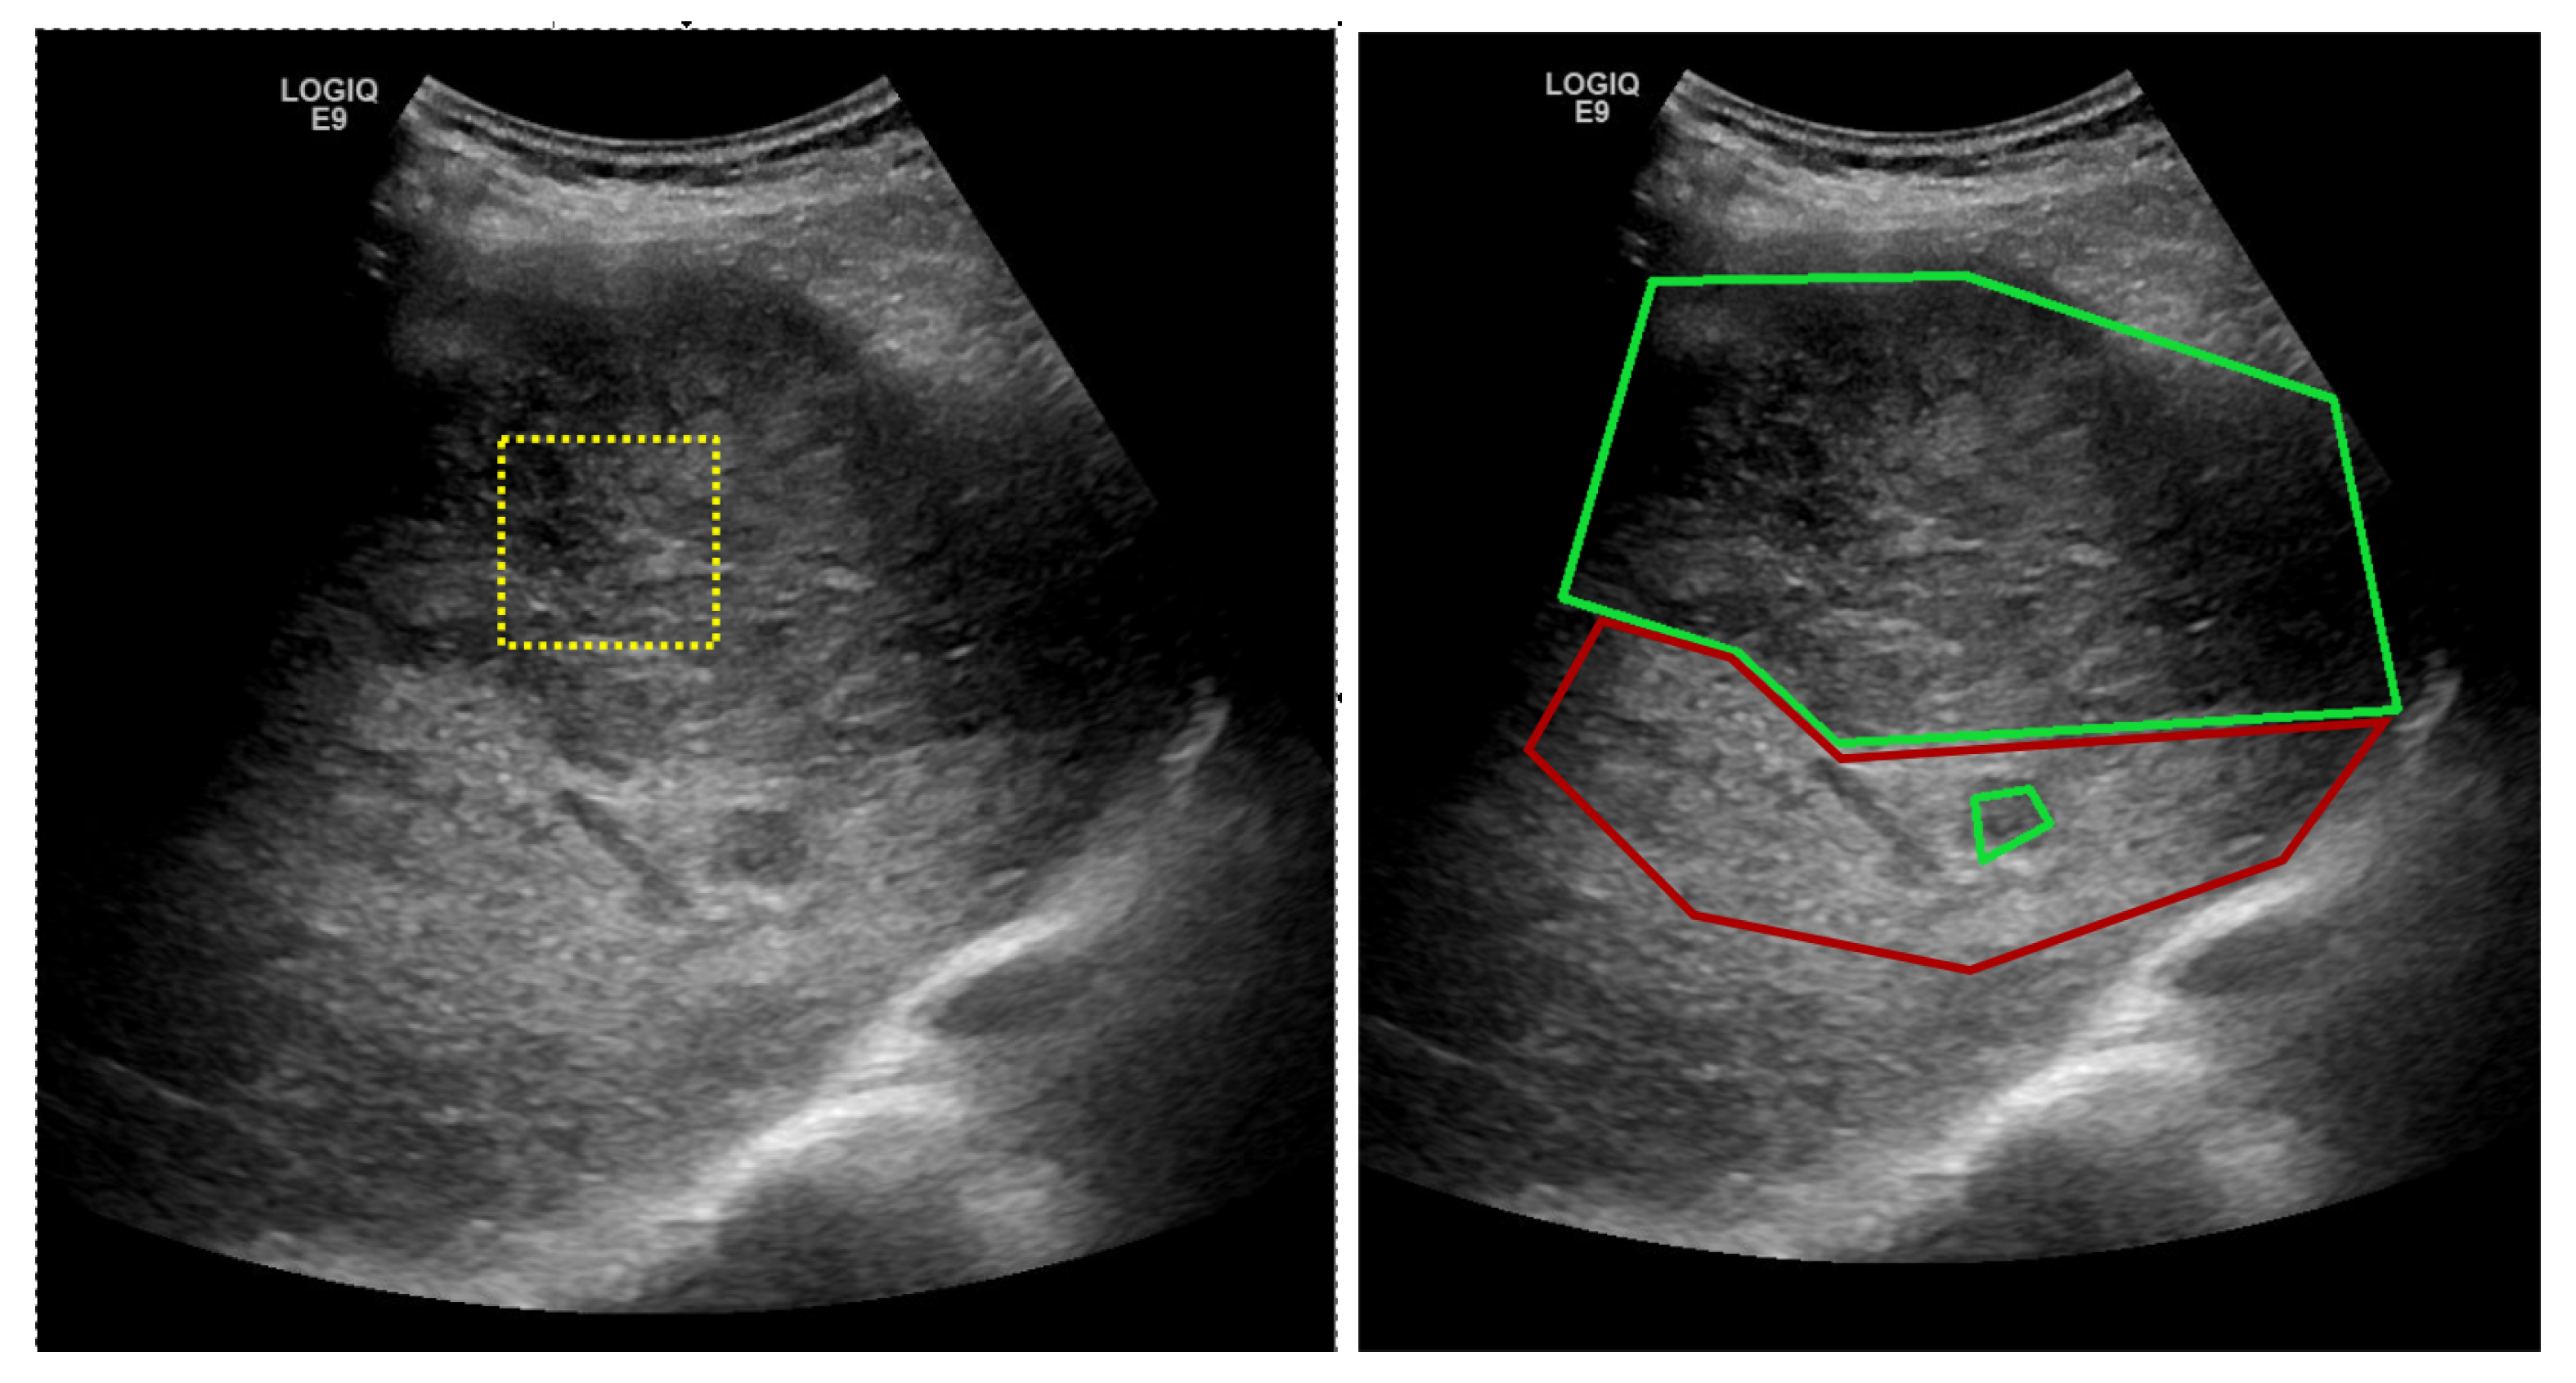

In ultrasound images, HCC usually appears as a hyperechogenic, inhomogeneous structure, due to the interleave of various tissue types, such as necrosis, fibrosis, active growth tissue, fatty cells [1]. As it can be noted from Figure 1, the visual aspect within ultrasound images of the PAR and HCC presents relevant features that characterize textures, such as finesse, coarseness, smoothness, surface granulation, randomness, irregularity.

The human-based analysis of the regions in the ultrasound images made in order to find problematic areas such as HCC or PAR can be aided by an automatic recognition method, such as the one proposed in this paper. The medical specialist could select regions of interest, as shown by the yellow patch in Figure 1 and obtain a probability score, displayed as a color confidence map, for each selected region. The proposed method classifies regions of interest from the ultrasound images and can provide a confidence map over the whole ultrasonographic image.

• Two annotated ultrasound image datasets have been involved in this study. Due to medical and practical patient diagnosis reasons, the images have been collected with two different ultrasound devices (General Electric Logiq 9 and General Electric Logiq 7). The first dataset contains information collected from 200 patients, while the second employs 68 cases. For each patient at least 3 ultrasound images have been annotated by the medical specialists, so the HCC area within the image is well marked (as shown in Figure 1 right). Extensive experiments reveal the conclusion that deep-learning-based models overcome the classical machine-learning techniques bringing an improvement of 17% in sensitivity and an improvement of 20% in specificity.

In both datasets, the HCC was marked as a polygonal area in the image, as shown in Figure 1—right, and Figure 2—middle. For each ultrasound image, considering the marked HCC area, rectangular image patches(regions) have been selected, by means of a controlled sliding window procedure. Part of these patches are located inside the annotated area and they correspond to the HCC class. The samples of the generated patches are depicted in green in Figure 2. Other patches are in the immediate vicinity of the polygonal annotation, but outside the marked HCC area. They correspond to the PAR samples and are shown in red in Figure 2. Cases of healthy patients were not considered because, usually, HCC evolves on cirrhotic liver tissue, for patients already affected by cirrhosis. The medical specialists suggested a focus on these two cases—to make the differentiation between HCC and the cirrhotic parenchyma on which it evolved, while healthy tissues have not been included in this study.

Figure 1. (left) Ultrasound image for which the medical specialist can select a region of interest for which the HCC/PAR confidence is needed; (right) Ground truth area—HCC area inside the large green polygon and PAR on which it has evolved delimited by the red polygon.